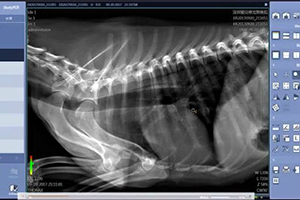

兽用DR 犬髋关节发育不良的诊断与治疗

犬髋关节发育不良是犬的常见的外科病,在家养宠物犬上发病率比较高,尤其是德国牧羊犬发病率最高,泰迪犬和中华田园犬也常见发病。该病不仅影响犬的正常行动,还极大影响犬的外型美观,如果不及时治疗,会继发慢性髋关节脱臼、慢性髋关节炎等其他疾病。近期本院治愈一例典型病例,在本文中与宠友朋友们分享。

一、病例情况

中华田园犬,一岁,5公斤,由于髋关节发育不良造成左后肢跛行,行动困难,影响日常生活,送上一家医院进行经保守治疗数周后未见有明显好转,综合分析各种因素后,经宠主同意,决定实施股骨头切手术。